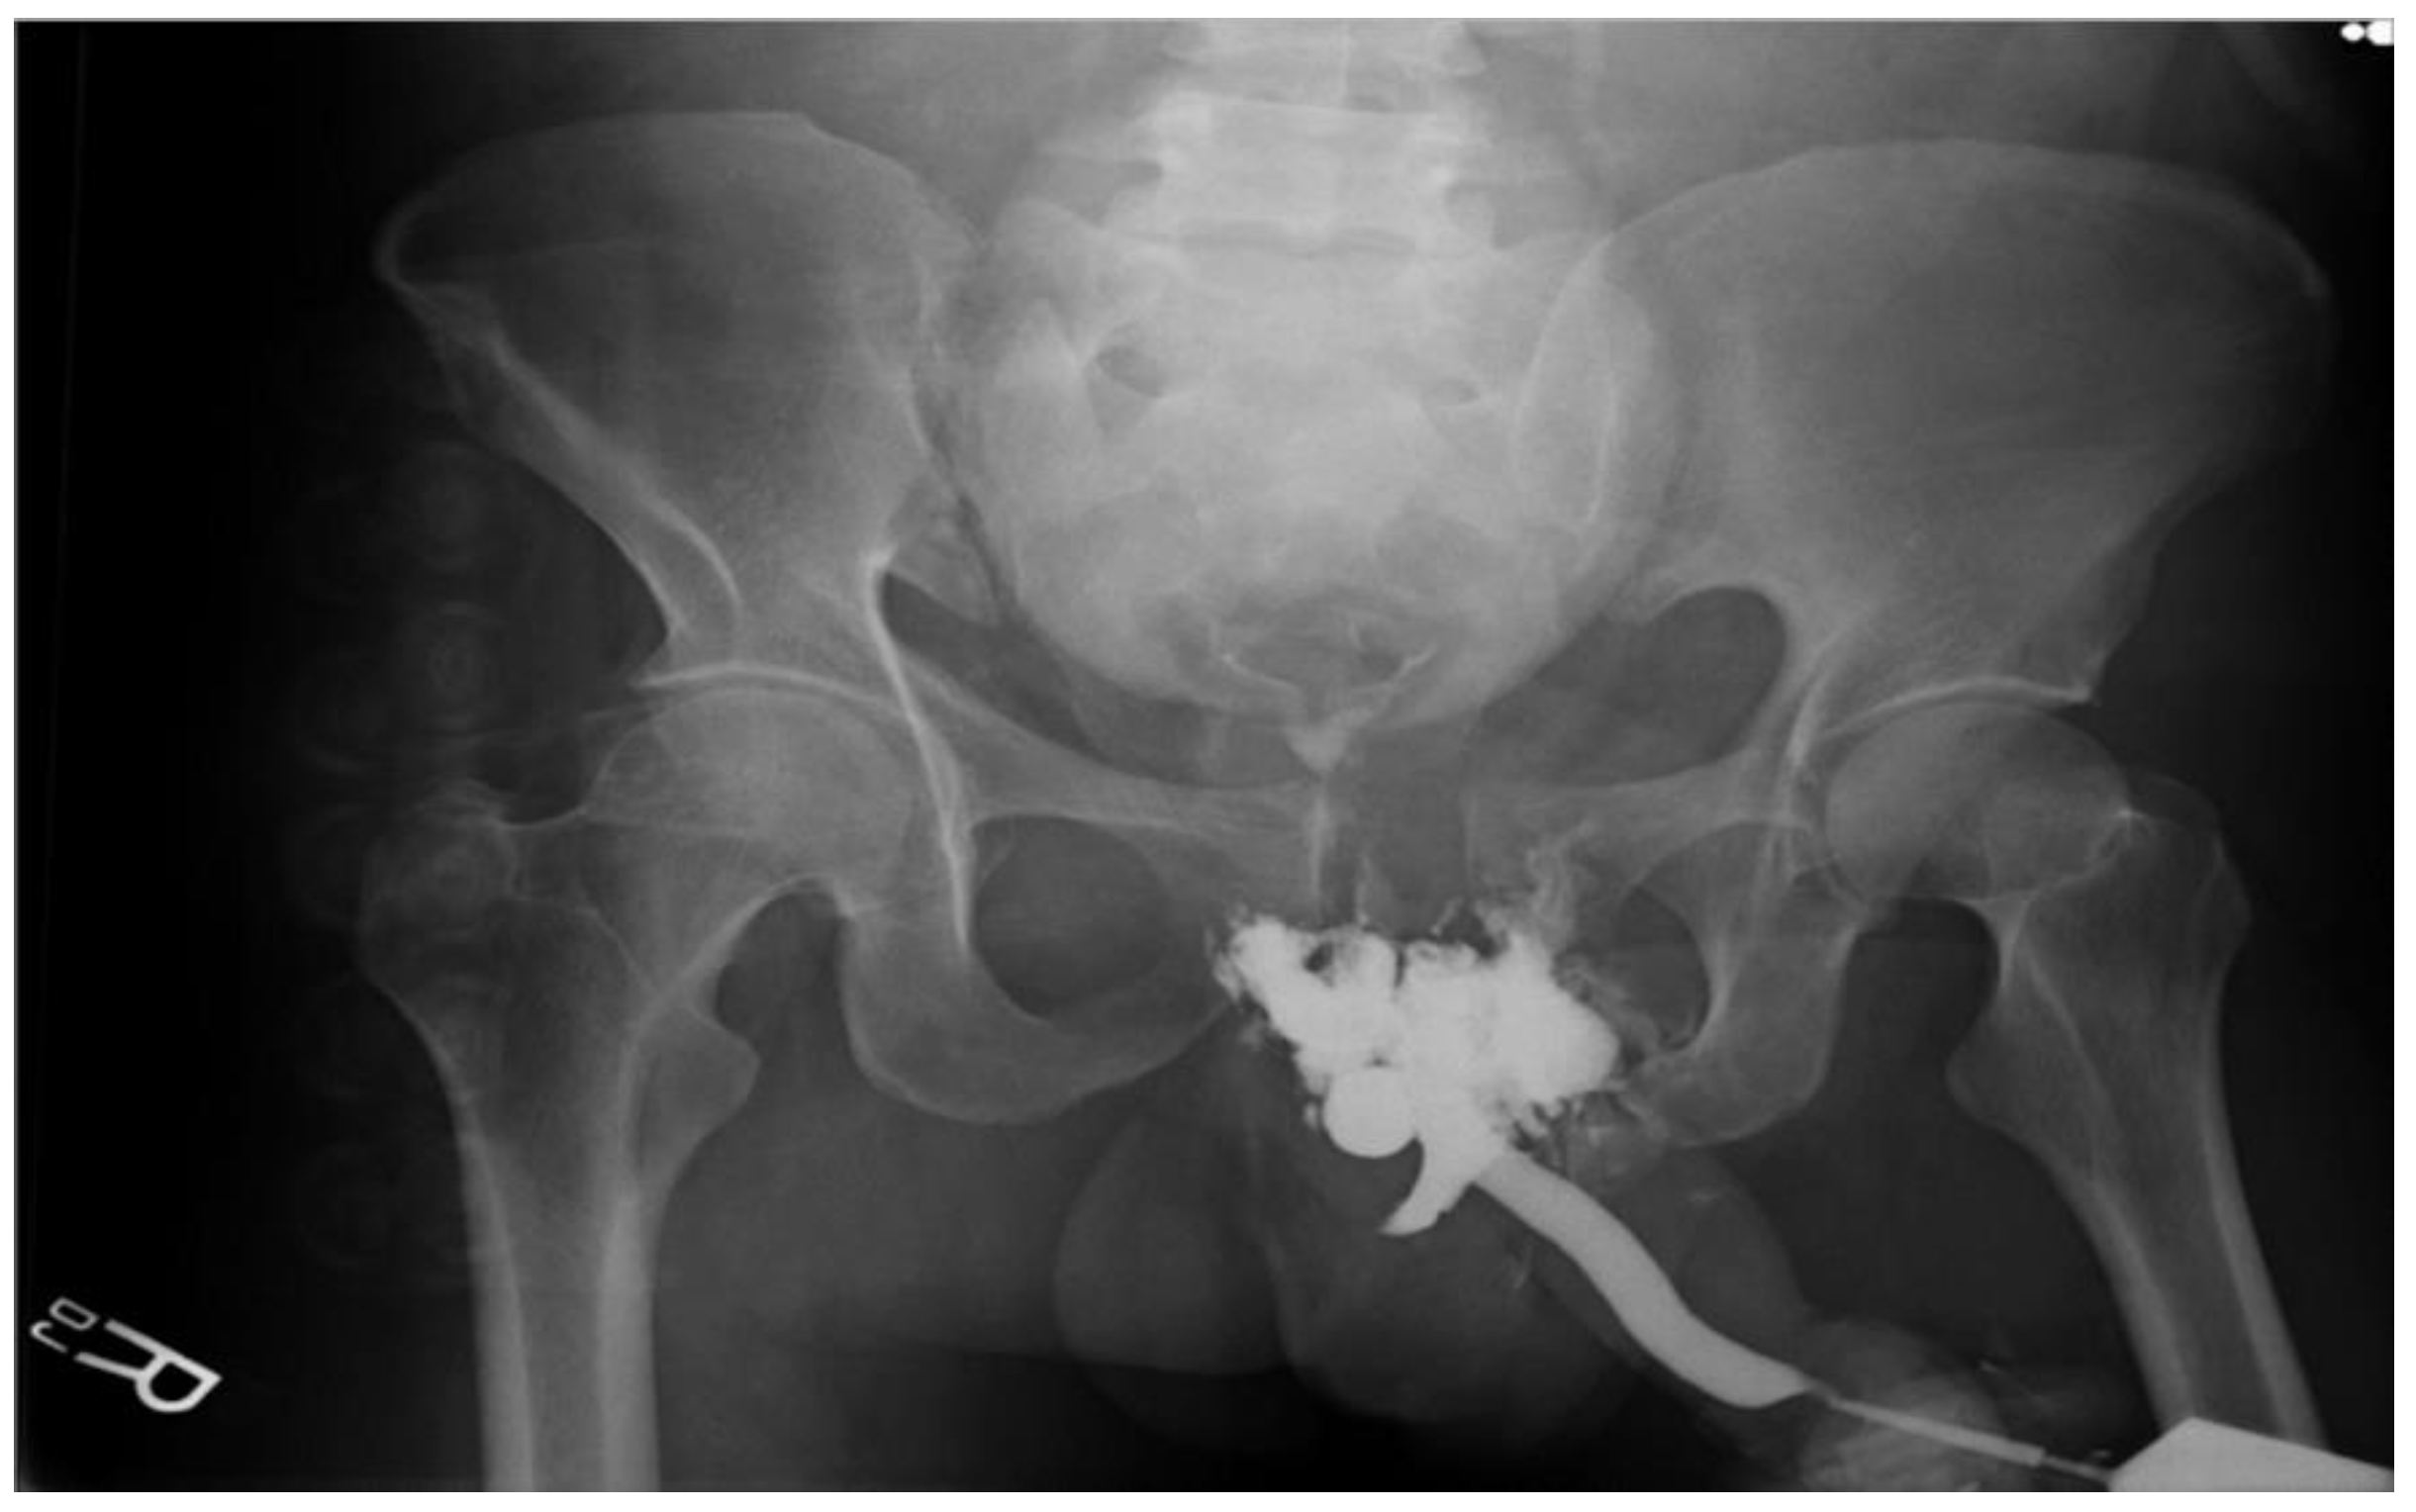

JCM Free FullText Urethral Injuries Diagnostic and Management Tape In Urethra  This is urine leakage that. This operation involves placing a piece of synthetic mesh material, like a.   the tension free vaginal tape (tvt) sling involves placing a tape of mesh underneath the urethra. Retropubic method (also called the. Each type takes about 30 minutes.  what is the synthetic vaginal mesh tape procedure?  a thin strip of mesh. Tape In Urethra.